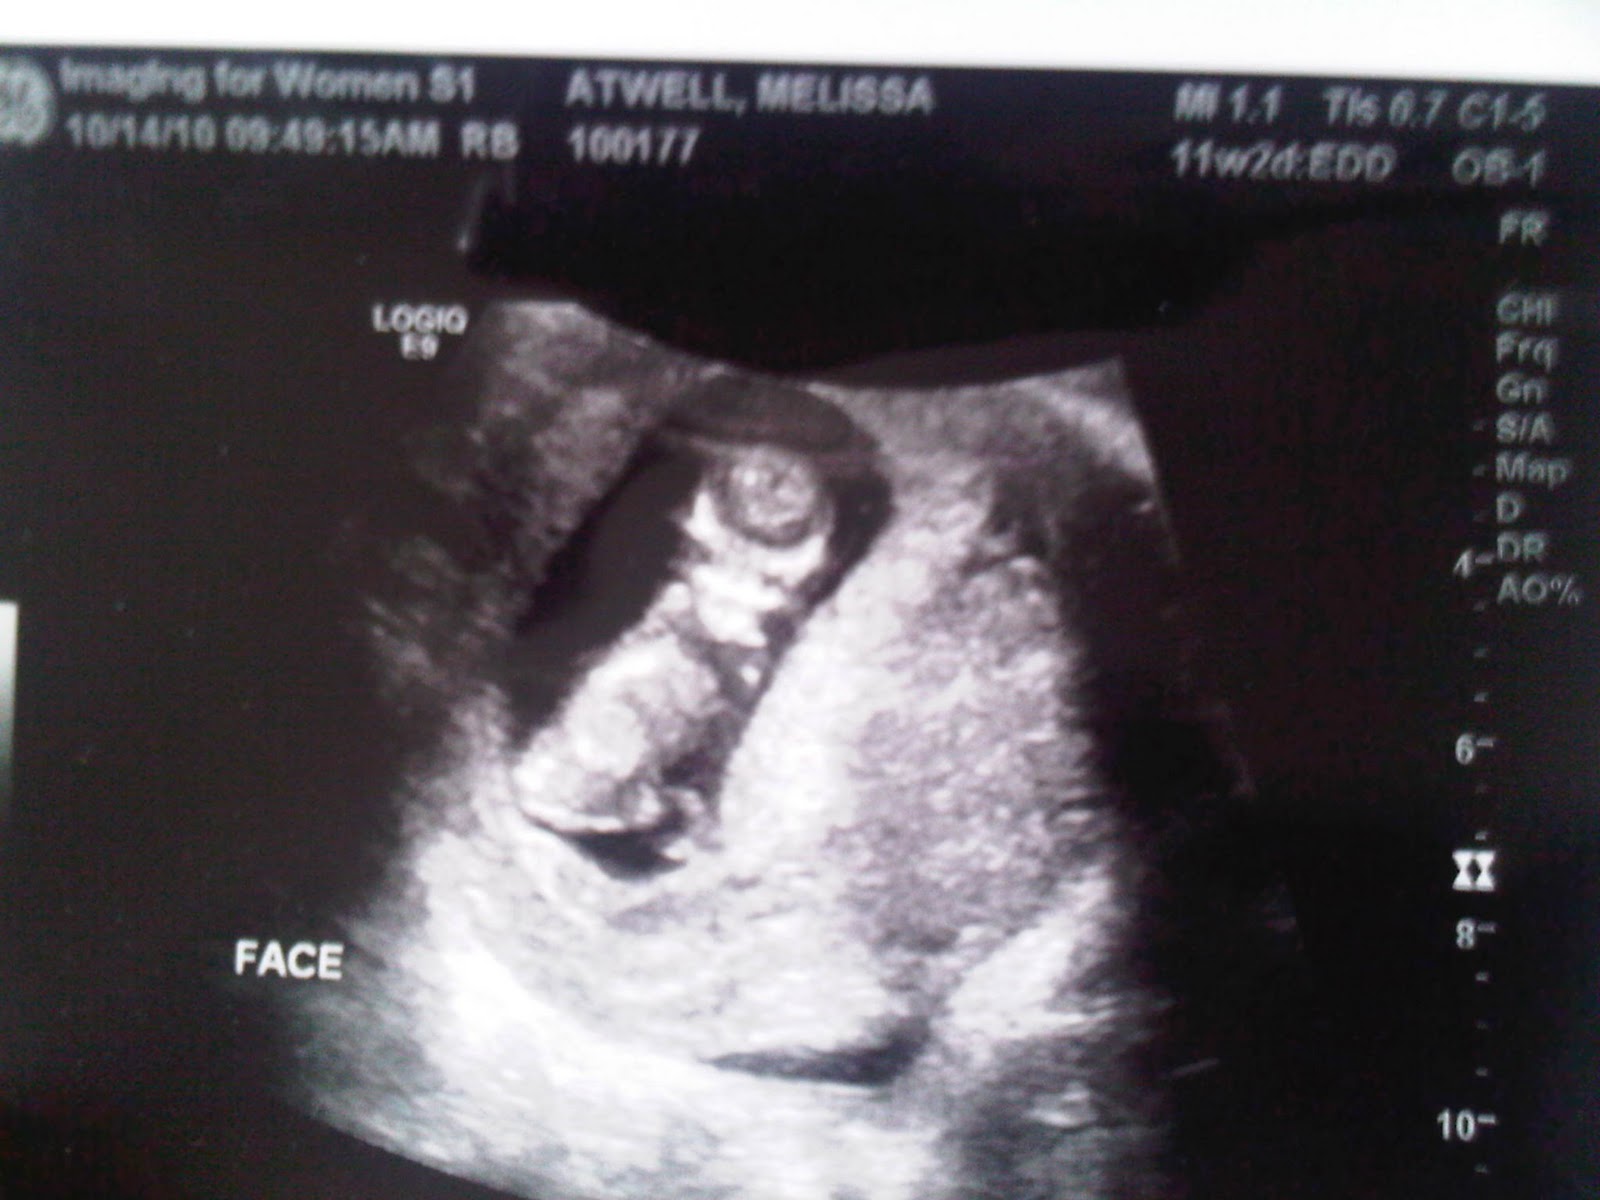

So I had an exam then he scheduled me an ultrasound the next morning (which by the way I feel all my time is spent going to appointments anymore) That morning I went to the ultrasound. This baby is crazy. It now looks much like a baby, it has it's two arms, and two leg, and its body shape, and it MOVES like crazy. The lady who did the ultrasound could not stop talking about how much it was moving, it was kicking its legs, standing up, turning around, we even got a picture of the face straight on (that picture was a bit scary) I asked if it was okay and normal to move that much, she stated all is okay heartbeat is normal, no stress on baby. But that she never sees them move around so much. Which scares me because when it gets bigger I will get to feel it constantly.

| the face looking at camera |